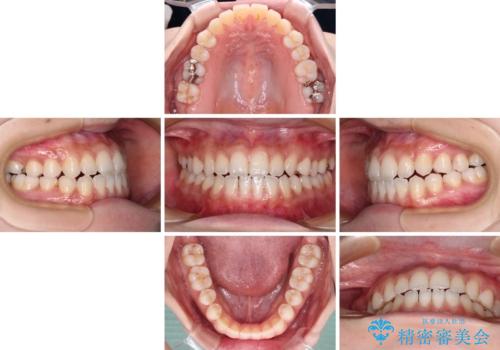

舌突出癖で口元が開いてしまう 舌トレーニングを行ったインビザライン矯正

- 1年5ヶ月

インビザラインにより上下の前歯の隙間を閉じていくこととしました。

上下の隙間に舌が入り込むことが、すきっ歯やオープンバイトの原因であったため、舌の筋肉のトレーニングも並行して行い、後戻りの抑制を図りました。